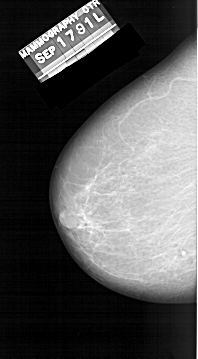

A_1309_1.LEFT_CC

LEFT_CC LINES 5731 PIXELS_PER_LINE 3166 BITS_PER_PIXEL 12 RESOLUTION 43.5 NON_OVERLAY